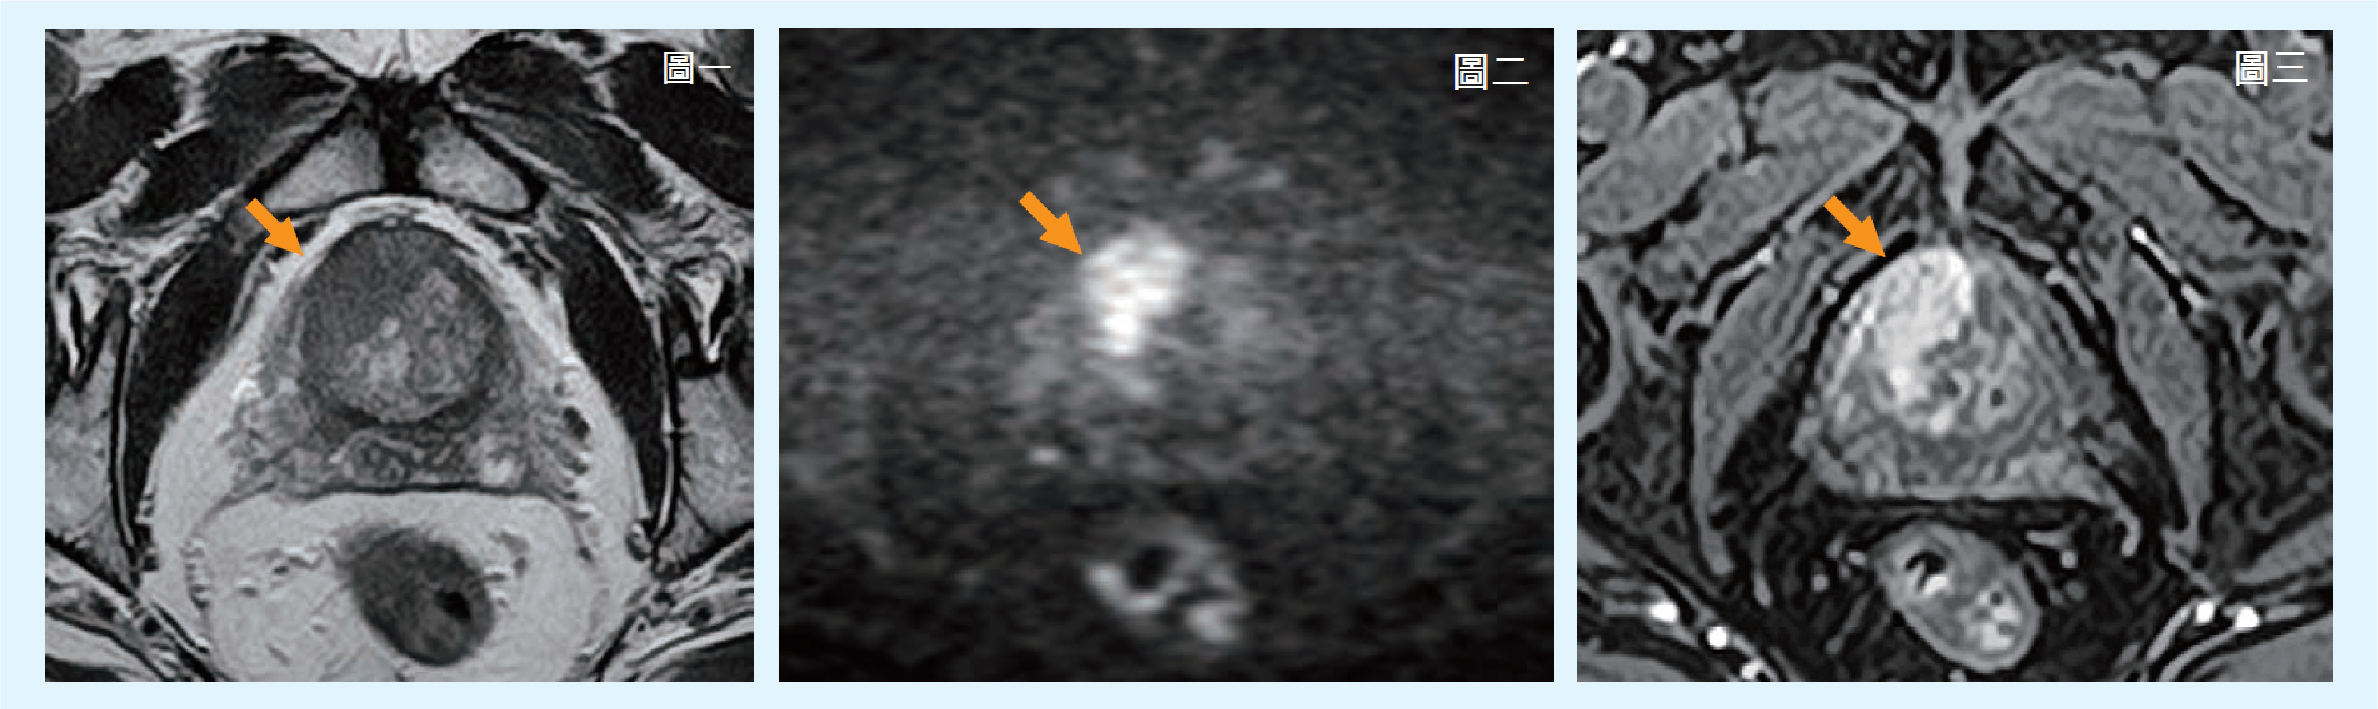

【案例一】

69歲男性,兩年前已因PSA異常(數值13)進行過切片檢查,病理報告為良性。近期因PSA數值持續升高(15),接受高階多參數攝護腺磁振造影檢查(mpMRI),在攝護腺前方偏右側,發現異常2.5公分低訊號腫塊,病灶在DWI擴散加權影像顯示異常高訊號,在動態對比增強影像中也顯示異常顯影。綜合以上影像特徵,經評分系統評估為5分,高度懷疑為攝護腺癌,建議進一步定位切片確診。